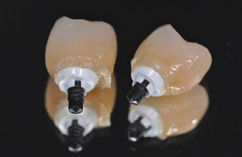

Für den Reentry wurde für das Einbringen des Gingivaformers eine minimale krestale Inzision angelegt (Abb. 13). Nach Abheilung der Weichgewebe (Abb. 14) konnte 2 Wochen später mit Reposition des Abformpfostens geschlossen abgeformt (Abb. 15) und das Meistermodel erstellt werden Da es sich um ein 2-teiliges Implantatsystem handelt und die Abutments ebenfalls aus hochfester ATZ-Keramik bestehen, lassen sich diese – falls nötig – entweder in der Praxis oder im Dentallabor durch Beschleifen individualisieren (Abb. 16). Für NobelPearl stehen sowohl gerade als auch 15° abgewinkelte Abutments mit 1 mm und 3 mm Gingivahöhe zu Verfügung. Im CAD/CAMVerfahren wurde eine monolithische Zirkonkrone aus Zolid FX (Amman Girrbach) mit okklusalem Zugang zum Schraubenkanal gefertigt (Dentallabor Studio für Zahntechnik, Dirk Tartsch).

Dr. Jens Tartsch

Wäre es gewünscht, die Schraube komplett entfernen zu können, muss die okklusale Zugangskavität der Krone den Durchmesser des Schraubenkopfes von 2,8 mm aufweisen. Bei einem Molaren ist diese Dimension meist unproblematisch, für einen schmaleren Prämolaren ist sie jedoch oftmals zu groß. In dem Fall wird die Schraube durch das Verkleben in die Konstruktion eingearbeitet. Es genügt dann eine Durchtrittsöffnung von 2,2 mm, die gerade noch den Zugang für den Schraubendreher ermöglicht (Abb. 17). Hierbei ist im Falle einer keramischen Verblendung auf eine Gerüstunterstützung der Überhänge zu achten. Sollte die eingearbeitete Schraube ausgetauscht werden müssen, kann die Abutment-Kronen-Verklebung durch Erwärmung im Ofen bei 120 °C einfach gelöst und in der Folge nach dem Auswechseln der Schraube neu geschaffen werden.

Verklebung der Krone

Nach der Einprobe von Abutment und Krone (Abb. 18 und 19) erfolgt ihre Verklebung analog einer Titanklebebasis entweder extraoral im Dentallabor oder, wie in diesem Fall, intraoral. Der Vorteil des Verklebens im Patientenmund liegt darin, dass eventuell auftretende Spannungen zwischen Abutment und Implantat abgefangen werden können. Solche Spannungen können bereits durch nicht ganz korrekte Reposition des Abformpfostens bei einer geschlossenen Abdrucknahme ausgelöst werden, durch kleine Ungenauigkeiten bei der Gestaltung der Kontaktpunkte oder aber auch durch das – wie bei jedem Implantatsystem mehr oder weniger vorhandene – „Spiel“ zwischen Implantat, Abformpfosten, Laborimplantat und Abutment. Dabei kann Titan als elastisches Metall solche „Mikrospannungen“ eher ausgleichen als die harte, nicht elastische Keramik.

Für das Verkleben wird das Abutment mit der Originalschraube bei nur leichtem Anzugstorque per Hand auf dem Implantat befestigt. In unserer Praxis hat es sich bewährt, das Abutment bzw. den Schraubenkanal mit Teflonband (Firma Rothenberger) zu verschließen (Abb. 20). Das Teflonband lässt sich fast schon plastisch modellieren und verschließt den Zugang zuverlässig. Überhänge oder Unterfüllung sind dabei zu vermeiden. Nach hersteller- und materialgemäßer Konditionierung wurden Abutment und Kronen mit geeigneten Kunststoffzementen (hier: RelyX unicem, 3M) verklebt. Das Vorgehen entspricht der Verklebung von keramischer Restauration mit einer Titanklebebasis. Nach dem Verkleben wird das Teflonband durch die Zugangskavität entfernt (Abb. 21).

Definitive Eingliederung

Die mit dem Abutment verklebten Restaurationen konnten nun entnommen, Zementüberschüsse (Abb. 22) sicher entfernt und die Übergänge von Krone zu Abutment poliert werden. Für die definitive Eingliederung ist der für die Abutmentschraube vorgegebene Anzugstorque von 25 Ncm einzuhalten. Nach erneutem Auffüllen der Schraubenkanäle wiederum mit Teflonband wurden die Zugangskavitäten in ebenfalls üblicher Weise mit Komposit verschlossen. Das Ergebnis sind im vorliegenden Fall 2 metall- und zementfreie, verschraubte und reversible Einzelzahnrestaurationen (Abb. 23). Bei dem routinemäßig durchgeführten Follow-up 6 Monate nach Eingliederung zeigte sich eine an beiden Implantatpositionen reizlose Weichgewebssituation (Abb. 24a und b) und in den radiologischen Kontrollaufnahmen stabile periimplantäre Knochenverhältnisse (Abb. 25a und b).